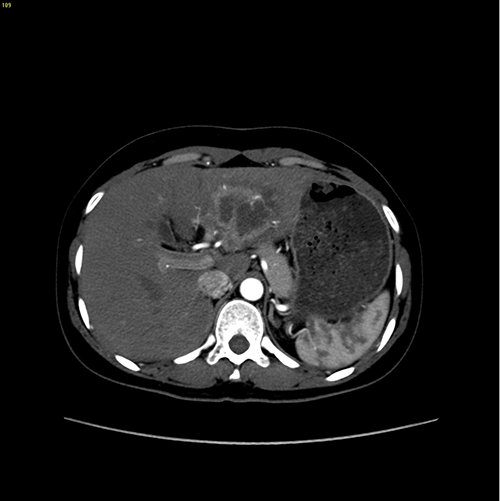

左肝肝癌---扩大左半肝切除+尾状叶切除